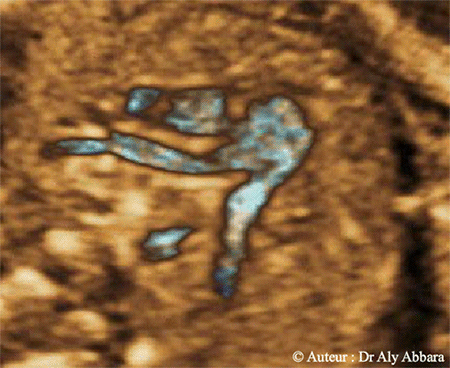

Cœur fœtal : coupe échographie avec Doppler montrant les trois gros vaisseaux

(artère pulmonaire, aorte et veine cave supérieure) avec la bifurcation de l'artère

pulmonaire en artères pulmonaires gauche et droite avec le canal artériel naissant

de la portion proximale de l'artère pulmonaire gauche :

• Coupe de la bifurcation de l'artère pulmonaire :

Les éléments anatomiques suivants peuvent être mis en évidence :

• Les trois gros vaisseaux cardiaques (de droite à gauche) Artère pulmonaire :

• la veine cave supérieure ;

• l'aorte dans sa portion ascendante, puis dans sa portion descendante Artère pulmonaire ;

• le tronc principal de l'artère pulmonaire (AP) Artère pulmonaire .

• La bifurcation de l'artère pulmonaire (AP) en deux branches :

• l'artère pulmonaire droite qui se dirige vers le poumon droit en passant derrière la coupe transverse de l'aorte ascendante et la veine cave supérieure ;

• l'artère pulmonaire gauche qui se dirige vers le poumon gauche ;

• la portion proximale de l'artère pulmonaire gauche se prolonge vers l'arrière par le canal artériel ; ce dernier se jette dans l'aorte (la partie distale de la crosse de l'aorte).